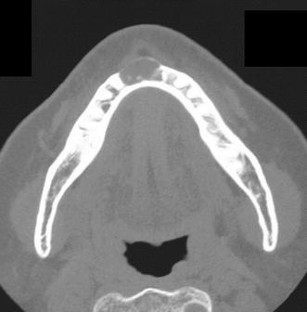

Glandular odontogenic cyst (GOC) is a rare odontogenic cyst derived from the odontogenic epithelium. GOC shows unpredictable and potentially aggressive behavior. Although enucleation and curettage are applied in most cases, the recurrence rate remains relatively high. Because a standard care procedure for GOC has not been established, we propose a new treatment procedure for GOC. In this case report, we describe a 62-year-old Japanese woman who suffered from GOC arising at the anterior region of her mandible and who was treated using the dredging method. She underwent enucleation and curettage twice using the dredging method with preservation of the teeth, which were involved with the lesion, but the lesion recurred 2 years later. In addition to enucleation and curettage, apicoectomy of the teeth was performed with a third dredging method procedure, and prognosis has been good with no recurrence for 18 months since the last treatment.

Fig. 1